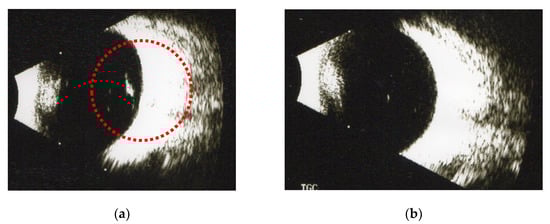

3.2. The Effect of Fruit Enzymes on the Change of Various Floaters